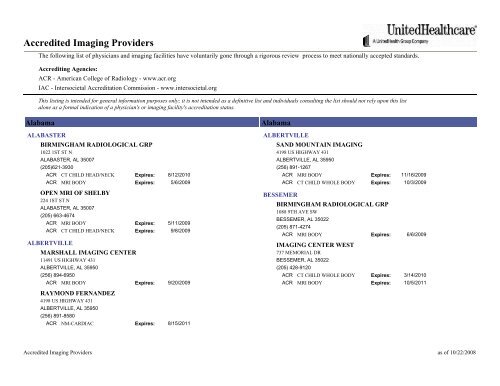

Accredited Imaging Providers Unitedhealthcareonline Com